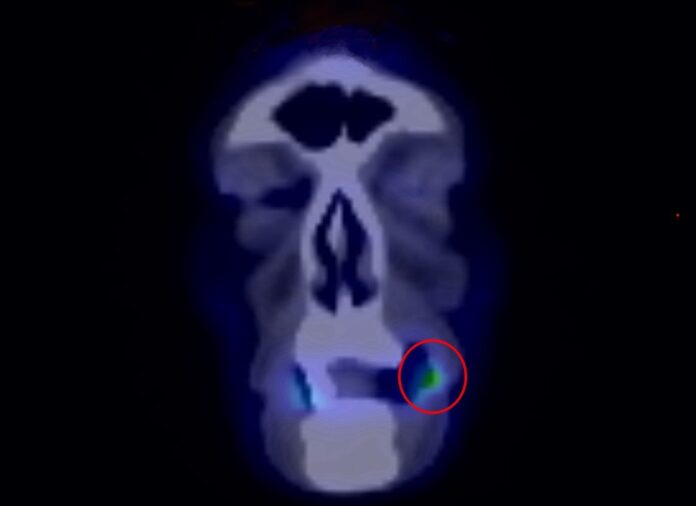

檢查發現,黃先生左側臉頰黏膜已有約2×1.5公分腫瘤,雖然疼痛感不明顯,卻已造成口腔異物感與張口受限。醫療團隊隨即安排切片檢查,證實為惡性腫瘤,後續透過電腦斷層與正子攝影確認分期,確診為第二期口腔癌。

針對病灶位置與侵犯範圍,林佳逢醫師安排手術完整切除腫瘤,並同步處理口角及部分臉部病灶,術後傷口癒合情況良好,目前持續門診追蹤。林佳逢醫師也提醒,第二期口腔癌,依據不同的口腔部位,仍有約有二到三成隱性轉移風險,術後規律追蹤與生活型態調整同樣重要。